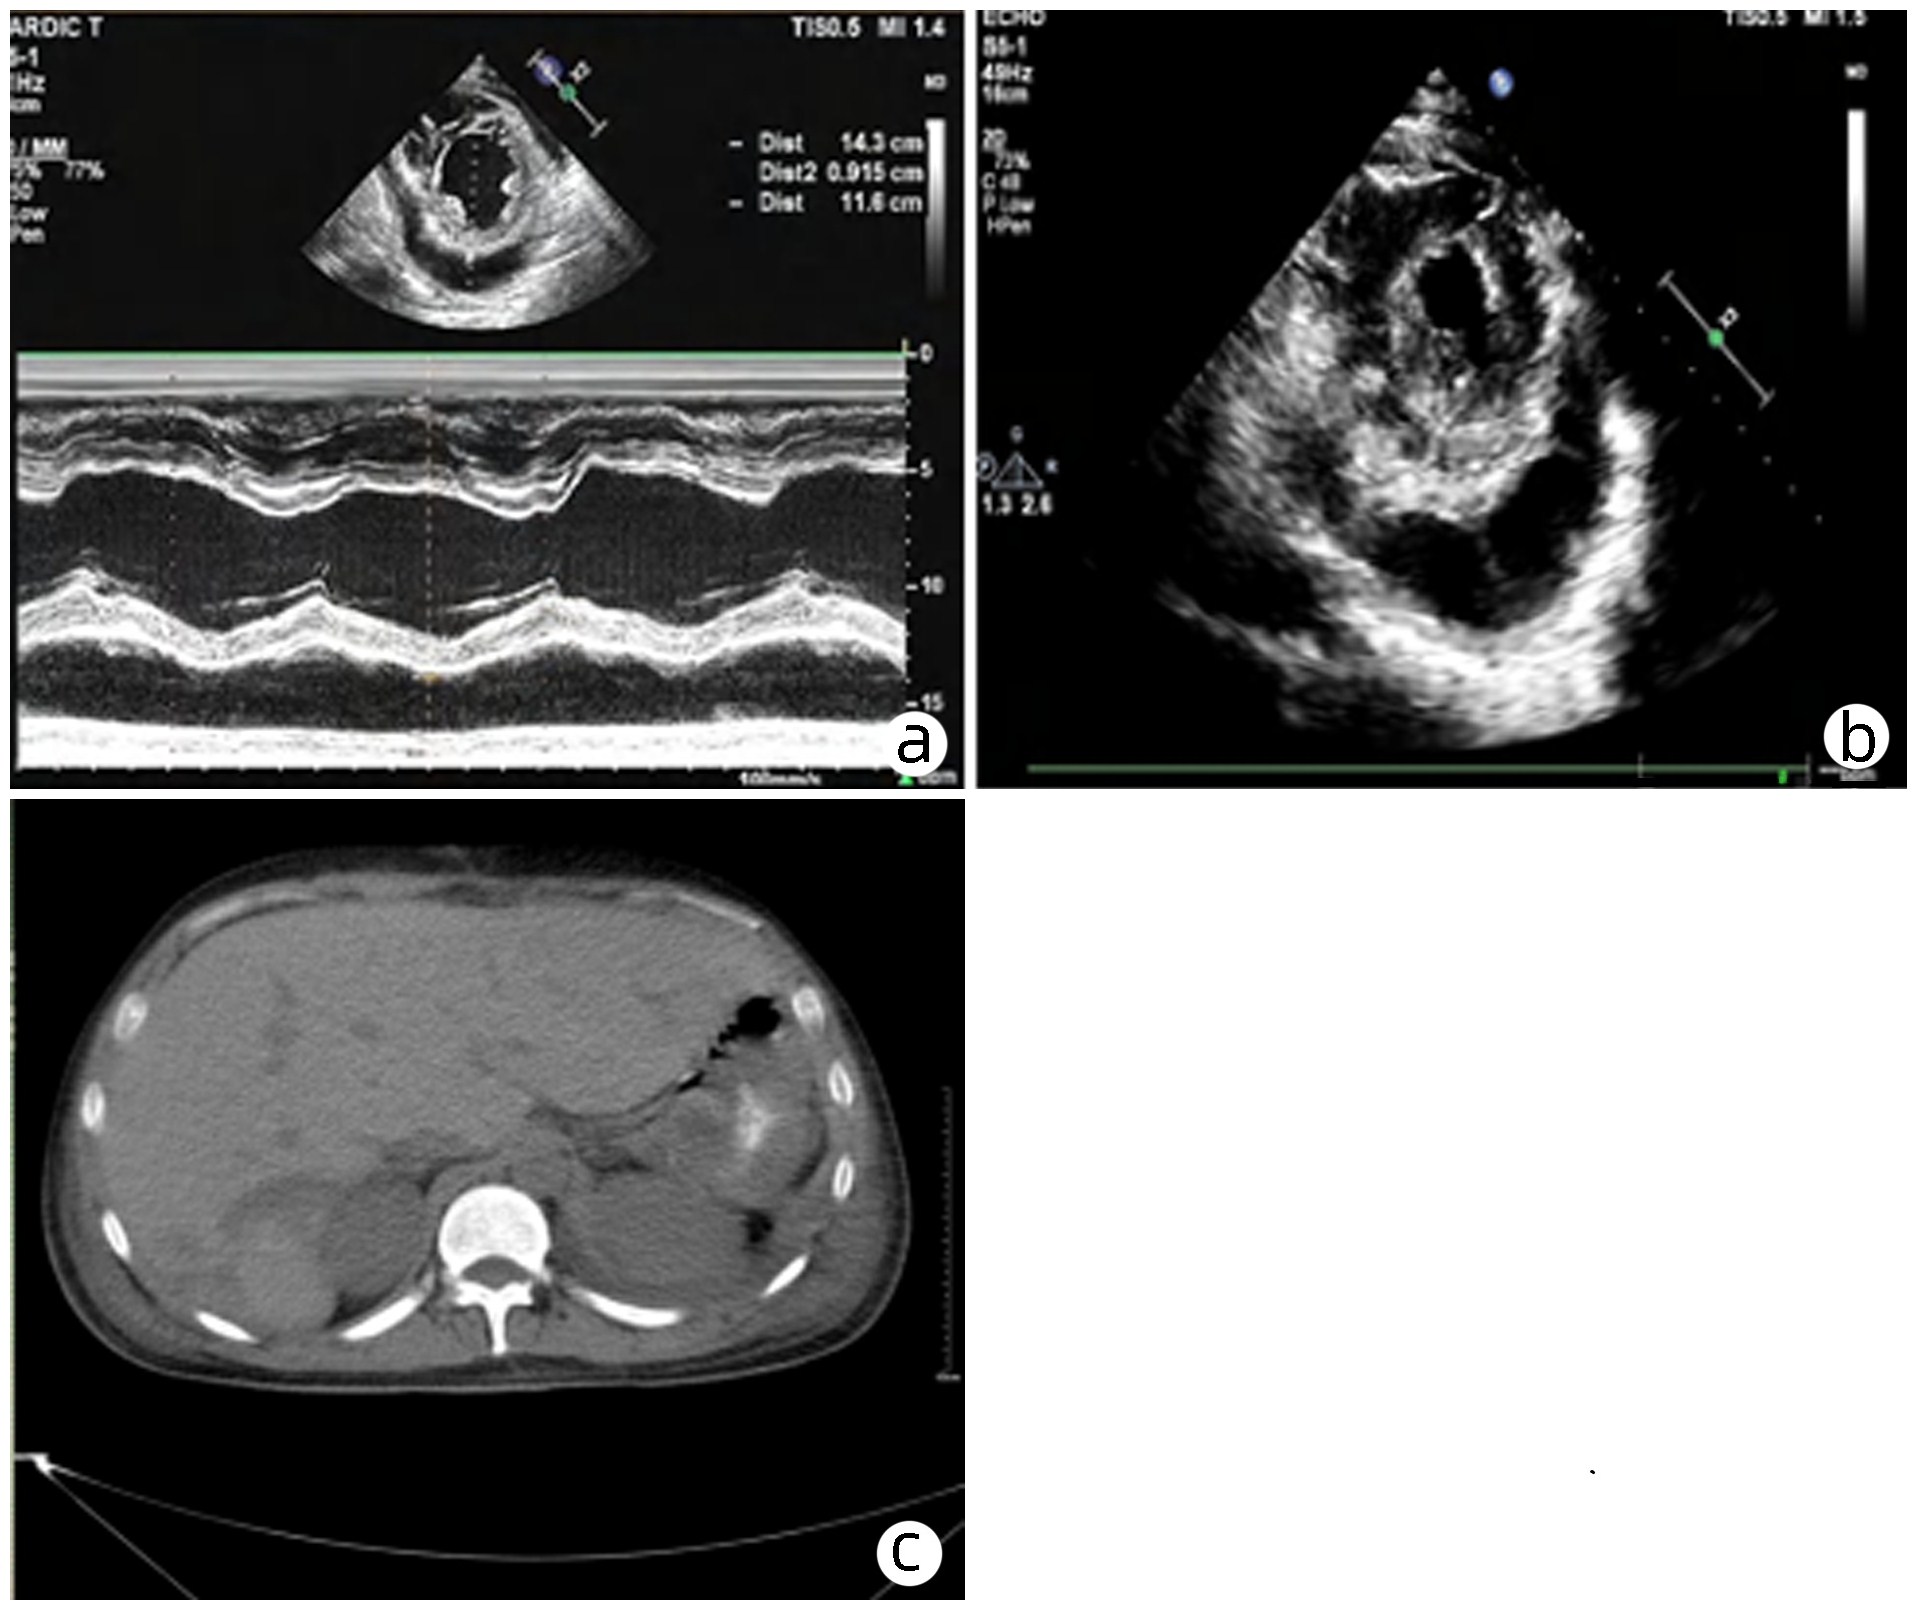

脓毒症合并自发性脾破裂出血1例报告

柳舟, 夏文芳, 詹丽英, 方小雨, 张亮, 詹娜, 禹荣, 黄丽, 朱垒

2023, 39(8): 1926-1931. DOI: 10.3969/j.issn.1001-5256.2023.08.024

摘要(1302) HTML (294) PDF (4249KB)(101)

摘要:

脓毒症所致重症感染往往导致多器官功能不全,如心功能不全、肾功能不全、肝功能损伤、脓毒症脑病、凝血功能障碍等。严重感染不仅导致全身炎症反应风暴,同时可诱发脾脓肿形成,甚至自发性脾破裂出血。自发性脾破裂起病隐匿,症状不典型,通常无明显外伤病史,临床容易漏诊。本例脓毒症患者突发左上腹疼痛、血红蛋白进行性下降,紧急完善腹部CT检查,考虑脾破裂出血。剖腹探查术术中发现腹腔大量积血,脾周血肿明显伴脾脏包膜撕裂,遂行全脾切除术。病理提示:脾脏慢性炎症细胞浸润,考虑脾脓肿伴出血。术后患者血色素平稳,腹痛症状明显好转。